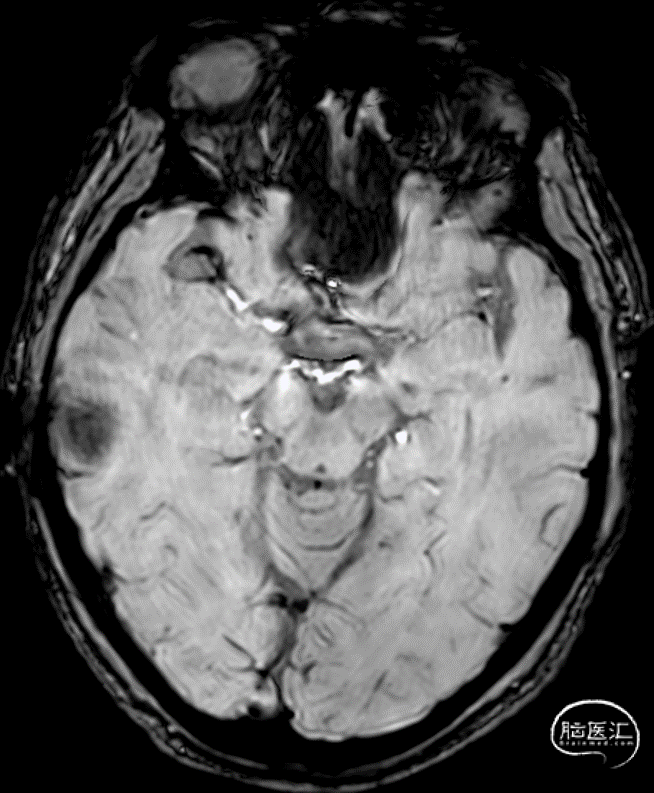

一般资料:男,56岁“反应迟钝、言语不清3月余”(2023.04.24入神经内科二病区)。2023.01.14家属发现反应迟钝、言语断续、答非所问,RMCA M1闭塞,急诊行血管内治疗。

20230114 PM 10:53 右侧大脑中动脉闭塞。

20230114 PM 11:29 右侧大脑中动脉闭塞。

20230114 侧枝循环代偿。

20230114 TICI 3 NeuroForm EZ 2.5×15尾端位于斑块内展开不理想。

20230117 AM 11:07 MR MMSE 6 MOCA 3;20230120出院反应迟钝好转不明显,中枢性面瘫。

20230420 PM 07:06 MRA+ASL。

20230425 PM 15:21 HR-MRI T2。

20230425 HR-MRI VISTA+C。

20230426 PM 01:47 NeuroForm EZ展开不良部位明显狭窄。

20230426 NeuroForm EZ展开不良部位明显狭窄。